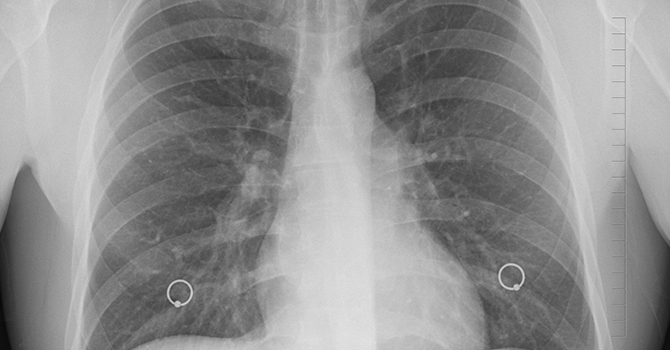

Associate professor of Epidemiology Rafael Meza was recently featured on "Lung Cancer Considered," a podcast produced by the International Association for the Study of Lung Cancer. The episode highlights Meza's recent study on smoke cessation programs and lung cancer screening.

Programs that help smokers kick the habit along with existing lung cancer screening efforts could reduce lung cancer mortality by 14% compared with screening alone, according to a new study.